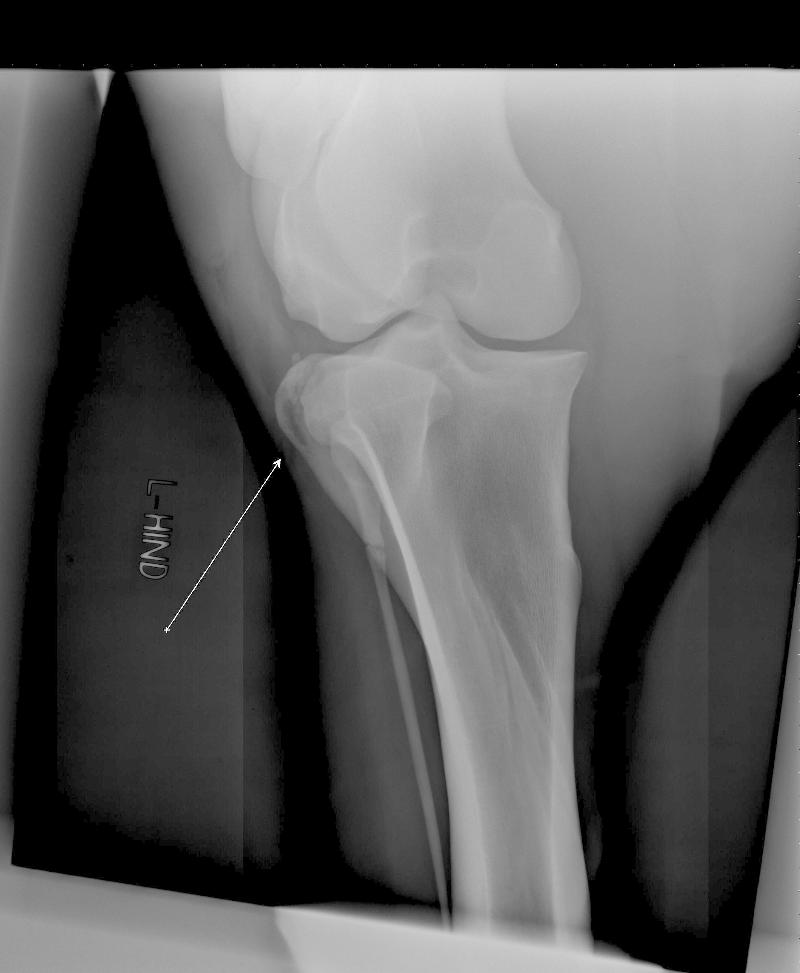

CSA1